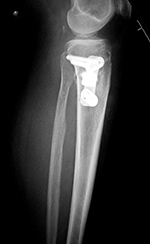

Metastatic renal cell carcinoma with pathologic fracture

Metastatic renal cell carcinoma pathologic fracture treated with curettage, bone cement, femur intramedullary nail, and distal locking screws

Bone cement in metastatic renal cell sarcoma